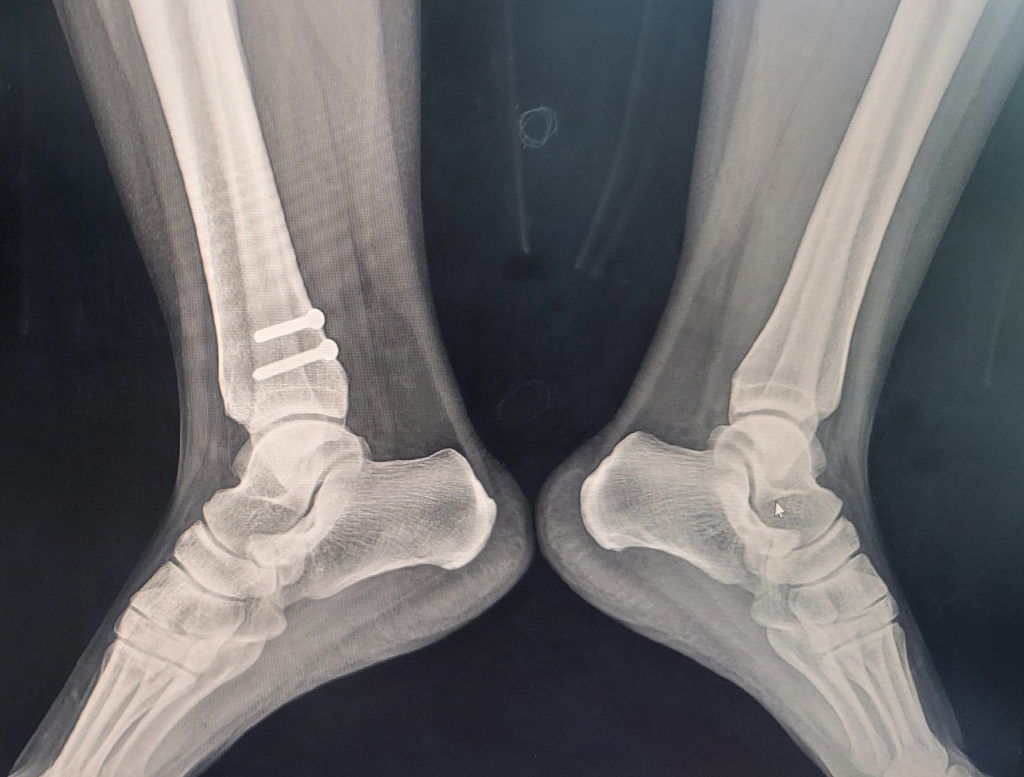

98년에 삽입한 핀이라면 핀 주위 조직과 유착이 상당할 수 있어 제거 수술은 일반적인 경우보다 난이도가 높을 수 있습니다.

하지만 통증이 지속된다면 핀 제거가 도움이 될 수 있으며 최근에는 최소절개 방식으로도 진행 가능하니 부담을 줄일 수 있습니다 정확한 위치와 상태를 ct나 엑스레이로 확인한 후 전문의와 수술 리스크 예후에 대해 상담하셔야 합니다!

해당 사진 한 장만 놓고 수술 가능 여부를 구체적으로 파악 및 판단하기는 어렵습니다. 수술을 희망하시는 병원에서 진료를 보시고 정밀 검사를 통해서 제거 가능한지 여부를 자세하게 파악해보아야 하겠습니다.